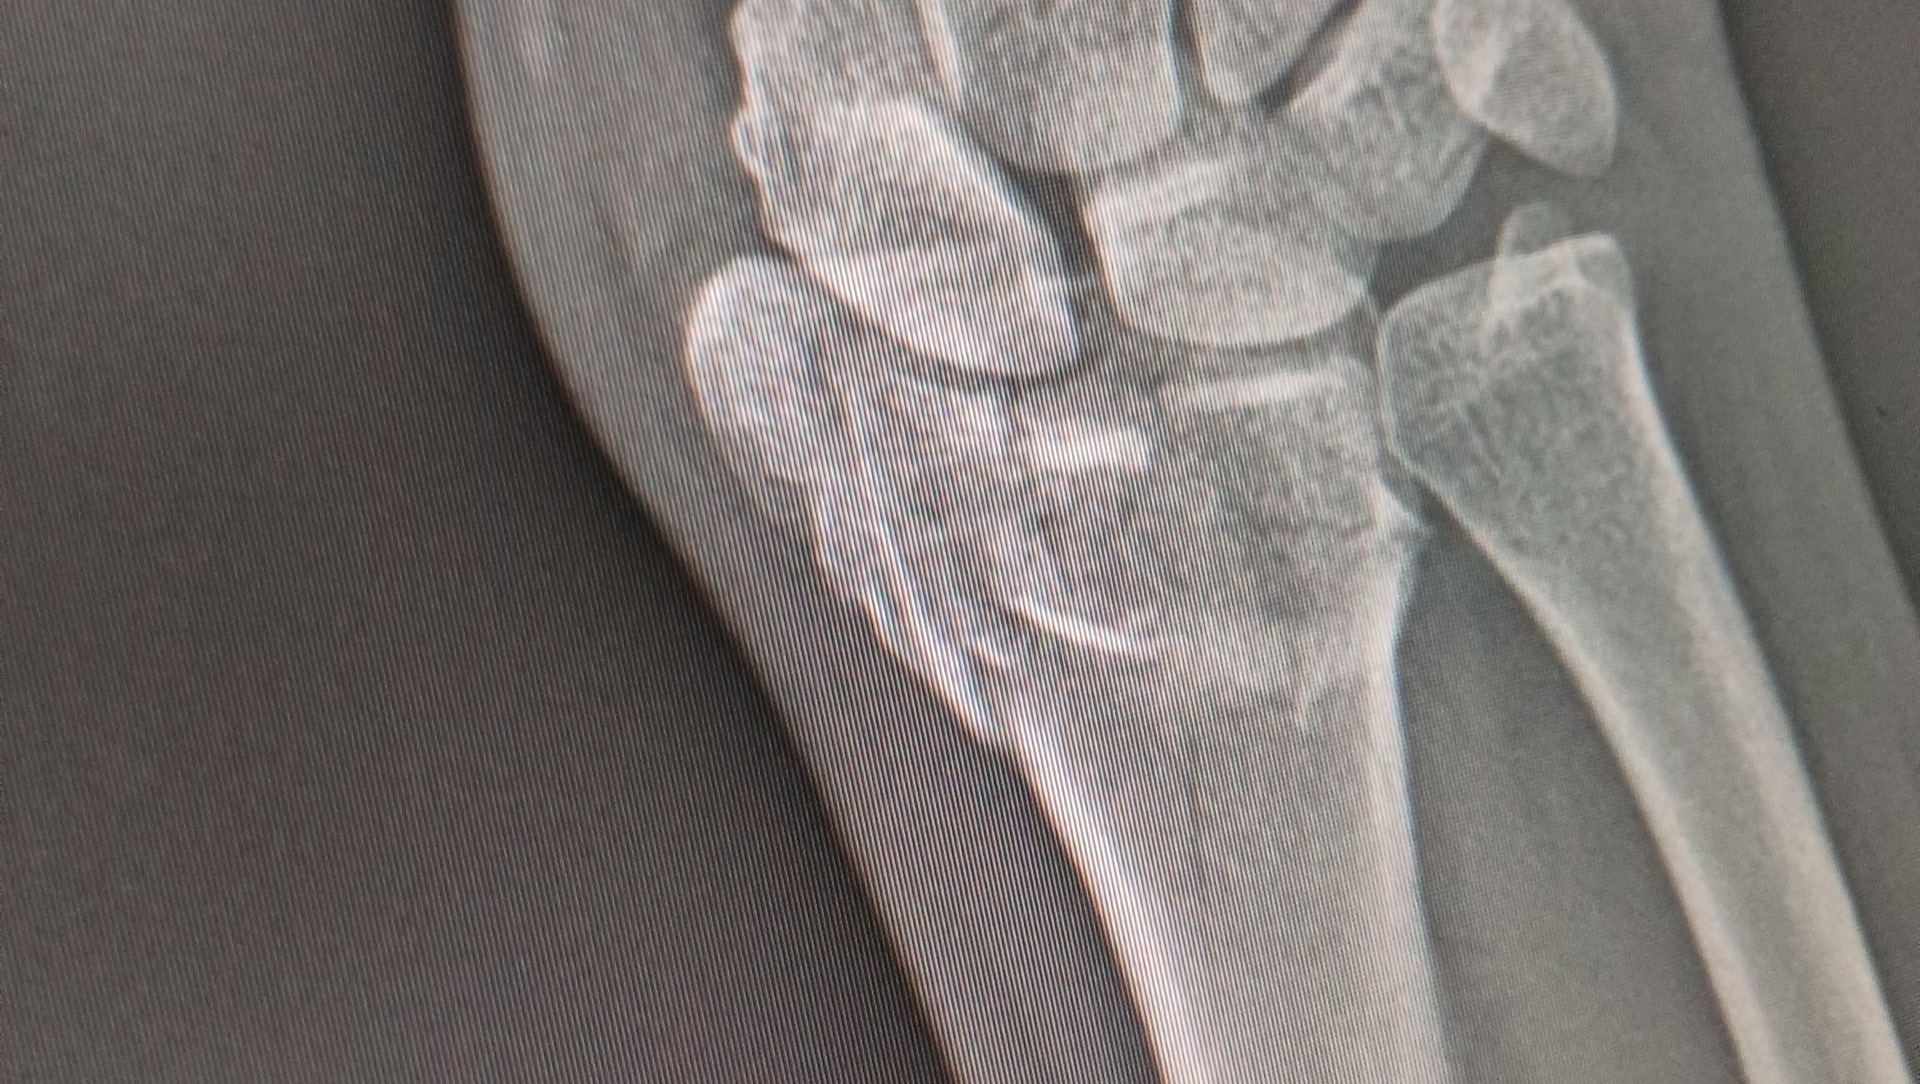

I have a Distal Radius Fracture... and it got fractured in many pieces and the pieces displaced. I'm currently dealing with pain but managing.

After consulting with the specialist, its been determined i will need surgery, which involves getting the wrist open and a metal plaque installed